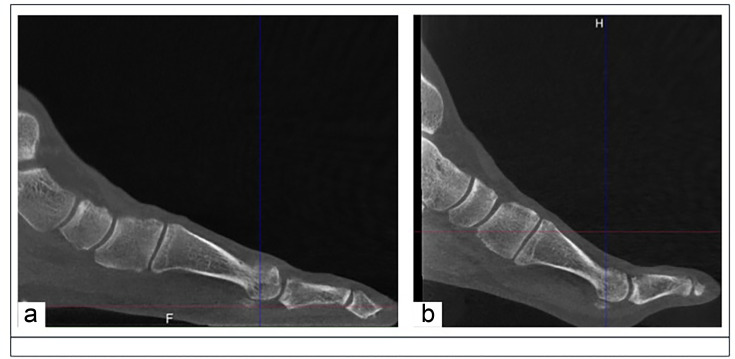

Aims: To evaluate how fore- and midfoot coronal plane alignment differs in feet with hallux valgus (HV), using 3DCT when measured in standard weightbearing (SWB) versus sesamoid view (SV) position, and to determine whether first metatarsophalangeal (MTP) dorsiflexion affects the relationship between the first metatarsal (M1) head and the sesamoid bones.

Methods: A consecutive series of 34 feet that underwent 3DCT in SWB and SV positions for symptomatic HV was assessed, of which four feet were excluded for distorted or incomplete images. Two foot and ankle clinicians independently digitized a series of points, and measured a series of angles according to a pre-defined protocol. Measurements include navicular pronation angle, M1 head (Saltzman angle), and metatarsosesamoid rotation angle (MSRA).

Results: The mean age of the 30 patients was 57.5 years (SD 13.4). The mean navicular pronation angle was significantly smaller in the SV position (9.6° (SD 4.4°)) compared to the SWB position (16.4° (SD 5.8°); p < 0.001). There was a difference in MSRA between the SWB and SV positions, revealing an increase in MSRA in 22 patients, while there was a decrease in eight patients. In patients where the MSRA increased, the mean Saltzman angle was 2.5° (SD 5.7°) lower in the SV position versus the SWB position, while in patients where MSRA decreased, the mean Saltzman angle was 3.4° (SD 3.6°) greater in the SV position versus the SWB position.

Conclusion: MTP dorsiflexion causes supination of the navicular, while other first ray parameters remain unchanged, and has a greater influence on the M1 head coronal alignment than on the sesamoids. MTP dorsiflexion induces axial rotations of M1, which vary in direction and magnitude from one patient to another.